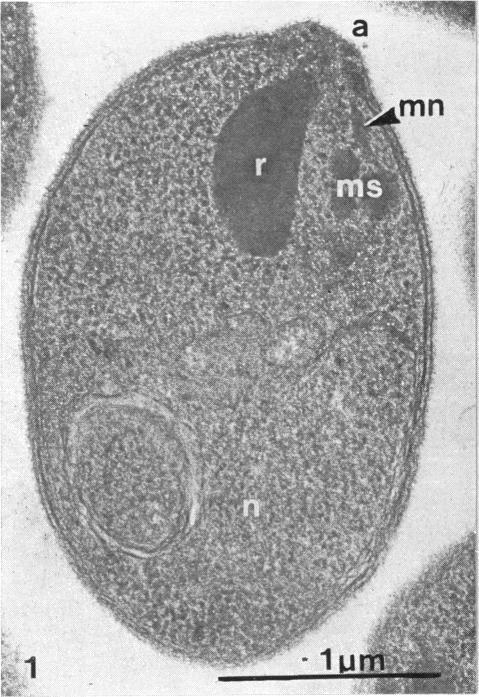

Previous observations on the process of invasion by P. knowlesi are briefly reviewed and new findings concerning the adhesion of parasites to erythrocytes and their intracellular passage are reported. Merozoites adhere to erythrocytes by means of a well-defined coat with the cytochemical characteristics of glycoprotein. This coat has receptors that engage in at least three distinct types of attachment. The ensuing invagination of the erythrocyte surface has two phases, the first consisting of an inward buckling of the membrane to form a vacuole and the second a rapid expansion to create the final parasitophorous vacuole inhabited by the trophic parasite. Some cytochemical evidence concerning the nature of the rhoptry complex is discussed in relation to these changes.

本文简要回顾了先前对诺氏疟原虫入侵过程的观察,并报告了有关寄生虫与红细胞粘附及其细胞内穿行的新发现。裂殖子通过具有糖蛋白细胞化学特征的明确被膜粘附于红细胞。该被膜具有参与至少三种不同类型附着的受体。随后红细胞表面的内陷有两个阶段,第一阶段是膜向内弯曲形成液泡,第二阶段是快速扩张以形成滋养寄生虫居住的最终的寄生泡。结合这些变化讨论了一些关于棒状体复合体性质的细胞化学证据。

Structure and invasive behaviour of Plasmodium knowlesi merozoites in vitro.体外诺氏疟原虫裂殖子的结构与侵袭行为

Parasitology. 1975 Dec;71(3):483-91. doi: 10.1017/s0031182000047247.